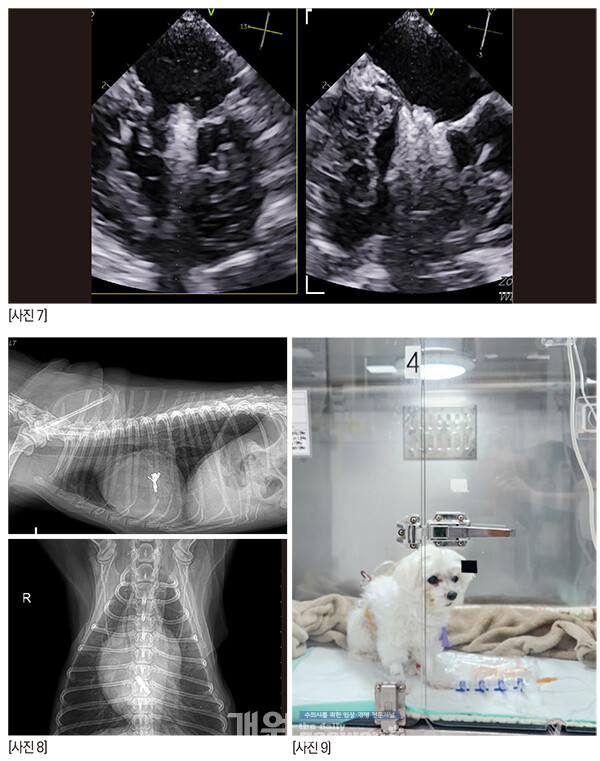

짱아의 방사선은 이렇다. 오랫동안 MMVD B2 로 유지되고 있다.

콩팥에는 결석이 있고, 복부초음파에서 콩팥은 점점 나이가 들어가고 있는 것은 확실하다.

[사진 8] P1-2 사이의 deep cleft like indentation 때문에 역류는 조금 남겠지만 술 전보다 나은 상황으로 만들고, 거기서 더 이상 진행만 안되면 충분히 괜찮다.매우 매우 걱정했지만 다행히 수술은 무사히 끝났고, 브이클램프를 close하는 시도도 한번으로 끝났다.